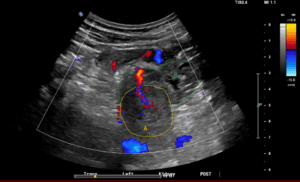

Since the second visit to the ED, the patient reported that the “hematoma” had recurred status-post aspiration and drainage but was smaller than it was initially and remained painful. Plastic surgery was consulted who noted palpable thrill at lateral aspect of the mass. On POCUS examination, the forehead mass was found to have pulsatile internal flow concerning for a vascularized structure such as an arteriovenous malformation (AVM) (Figure 2 and Supplemental Video S1). CTA was performed which revealed a 7 mm round pool of contrast at the lesion, supplied by an artery with a questionable draining vein, consistent with an AVM or less likely pseudoaneurysm (Figure 3). Given ongoing pain at the site of the soft tissue mass, the patient was planned for outpatient resection of the vascularized soft tissue mass with interventional radiology support.

Figure 2. A, B are long axis POCUS images of the right forehead soft tissue mass (B with color Doppler). C, D are short axis POCUS images (D with color Doppler). B and D demonstrate the “Ying-Yang” or “Pepsi” sign, which is due to bidirectional or turbulent blood flow.

POCUS can be helpful in the initial evaluation of a soft tissue mass as it can be used to distinguish some of the characteristic features of this broad differential diagnosis. For lipomas, one would expect to see a lack of blood flow on color Doppler with minimal or no growth on serial measurements using US [2]. While the shape and echogenicity of abscesses are variable, mobility of echogenic internal fluid contents when placing slight pressure with the ultrasound probe could lead to a higher clinical suspicion of abscess. Furthermore, surrounding edema in a cobblestone appearance can be seen secondary to the host inflammatory response [3]. Malignant soft tissue masses will grow on serial US measurements and are expected to be larger in nature when compared to other diagnoses one may be considering (>4.6 cm). Other common features of malignant masses include irregular borders, deep infiltration through surrounding tissue planes or structures, and increased vascularity on color Doppler [3,4,5]. Specific to vascular malformations, there were POCUS findings that this patent’s mass exhibited that helped narrow the differential: The “Ying-Yang” or “Pepsi” sign on color Doppler is due to bidirectional or turbulent flow (Figure 2B, 2D).  This has been reported in pseudoaneurysms but was seen in this case of suspected post-traumatic AVM [6].